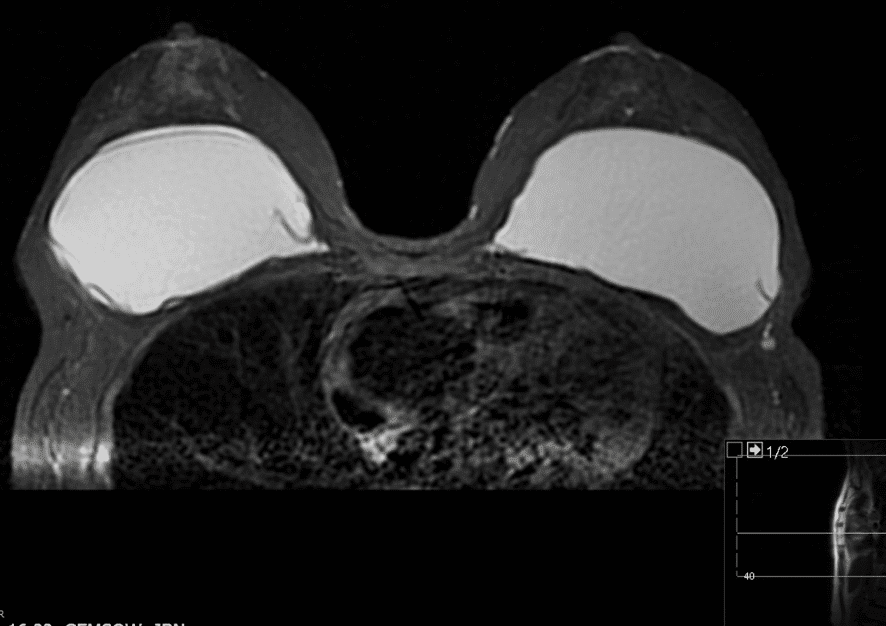

Silicone levels in the blood and breastmilk of women with implants are similar to those without implants, and breastfeeding is safe.  Patients may report concern with a ruptured implant in the setting of breastfeeding, particularly with extracapsular rupture of silicone implants.  Saline poses no risk and revision/replacement should be deferred until lactation is complete.  Deferment of revision of a ruptured silicone implant may also be safe, given exponentially higher silicone levels in cow’s milk and formula. If rupture is suspected, breast MRI is the preferred imaging modality for evaluation.  It is safe in lactation.

Rupture of silicone implant visualized on MRI.